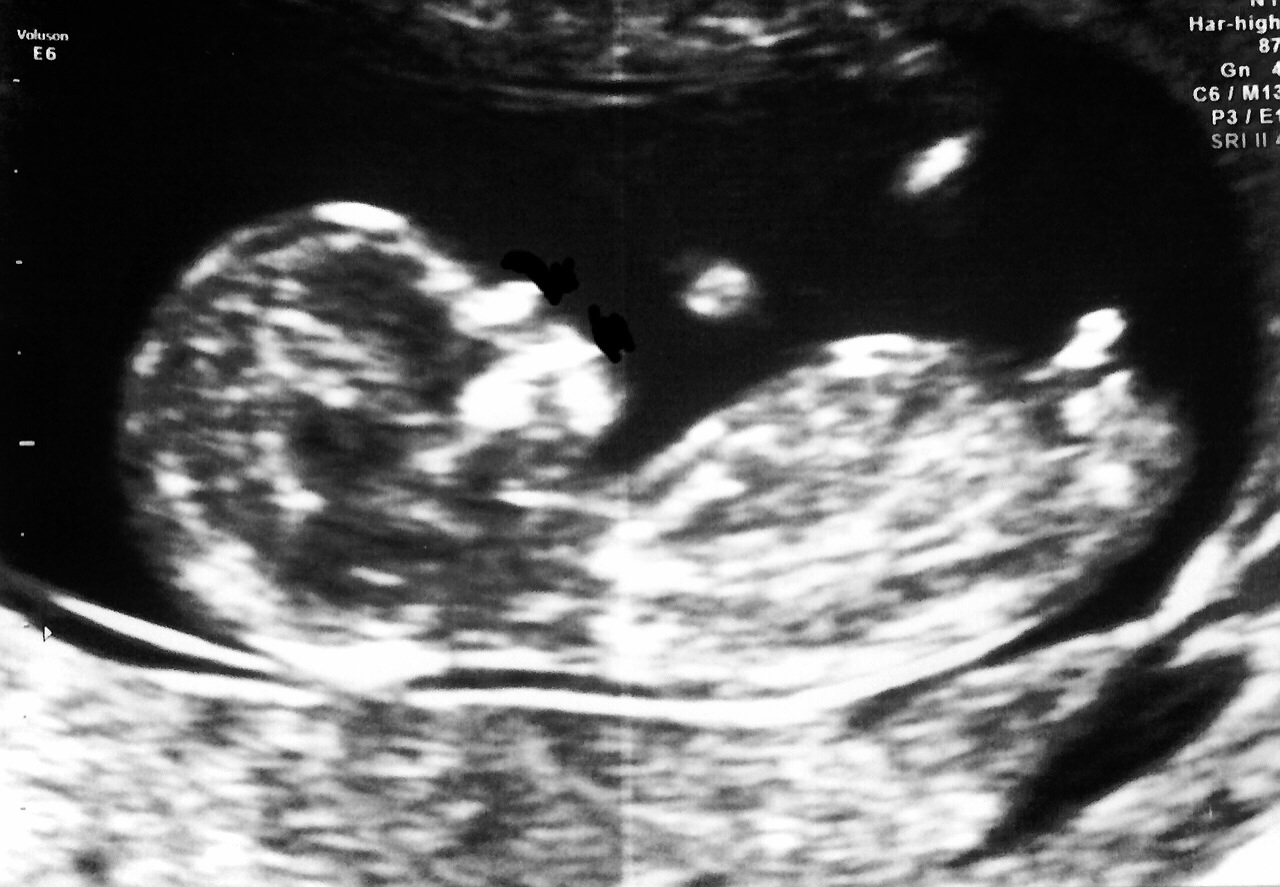

1st u/s pic at about 13w

2nd at 21w. Team blue! (Again!)